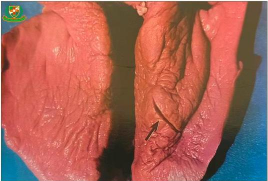

阿苯达唑(Albendazole)是一种广谱抗寄生虫药物,常用于治疗多种线虫、绦虫和吸虫感染。在反刍动物(如山羊)中,它常用于驱除肺丝虫(如羊仰口线虫 *Haemonchus contortus*、毛线虫 *Trichostrongylus* spp.、食道口线虫 *Oesophagostomum* spp. 等),这些寄生虫可引起严重的肺丝虫病或线虫性肺炎。

对于肺部寄生虫(如某些种类的肺线虫),效果可能不如对胃肠道线虫明显,但仍然有一定的驱虫作用。

有些肺丝虫(如牛肺线虫 *Dictyocaulus viviparus*)对阿苯达唑不敏感,可能需要使用其他药物如伊维菌素(Ivermectin)或芬苯达唑(Fenbendazole)。